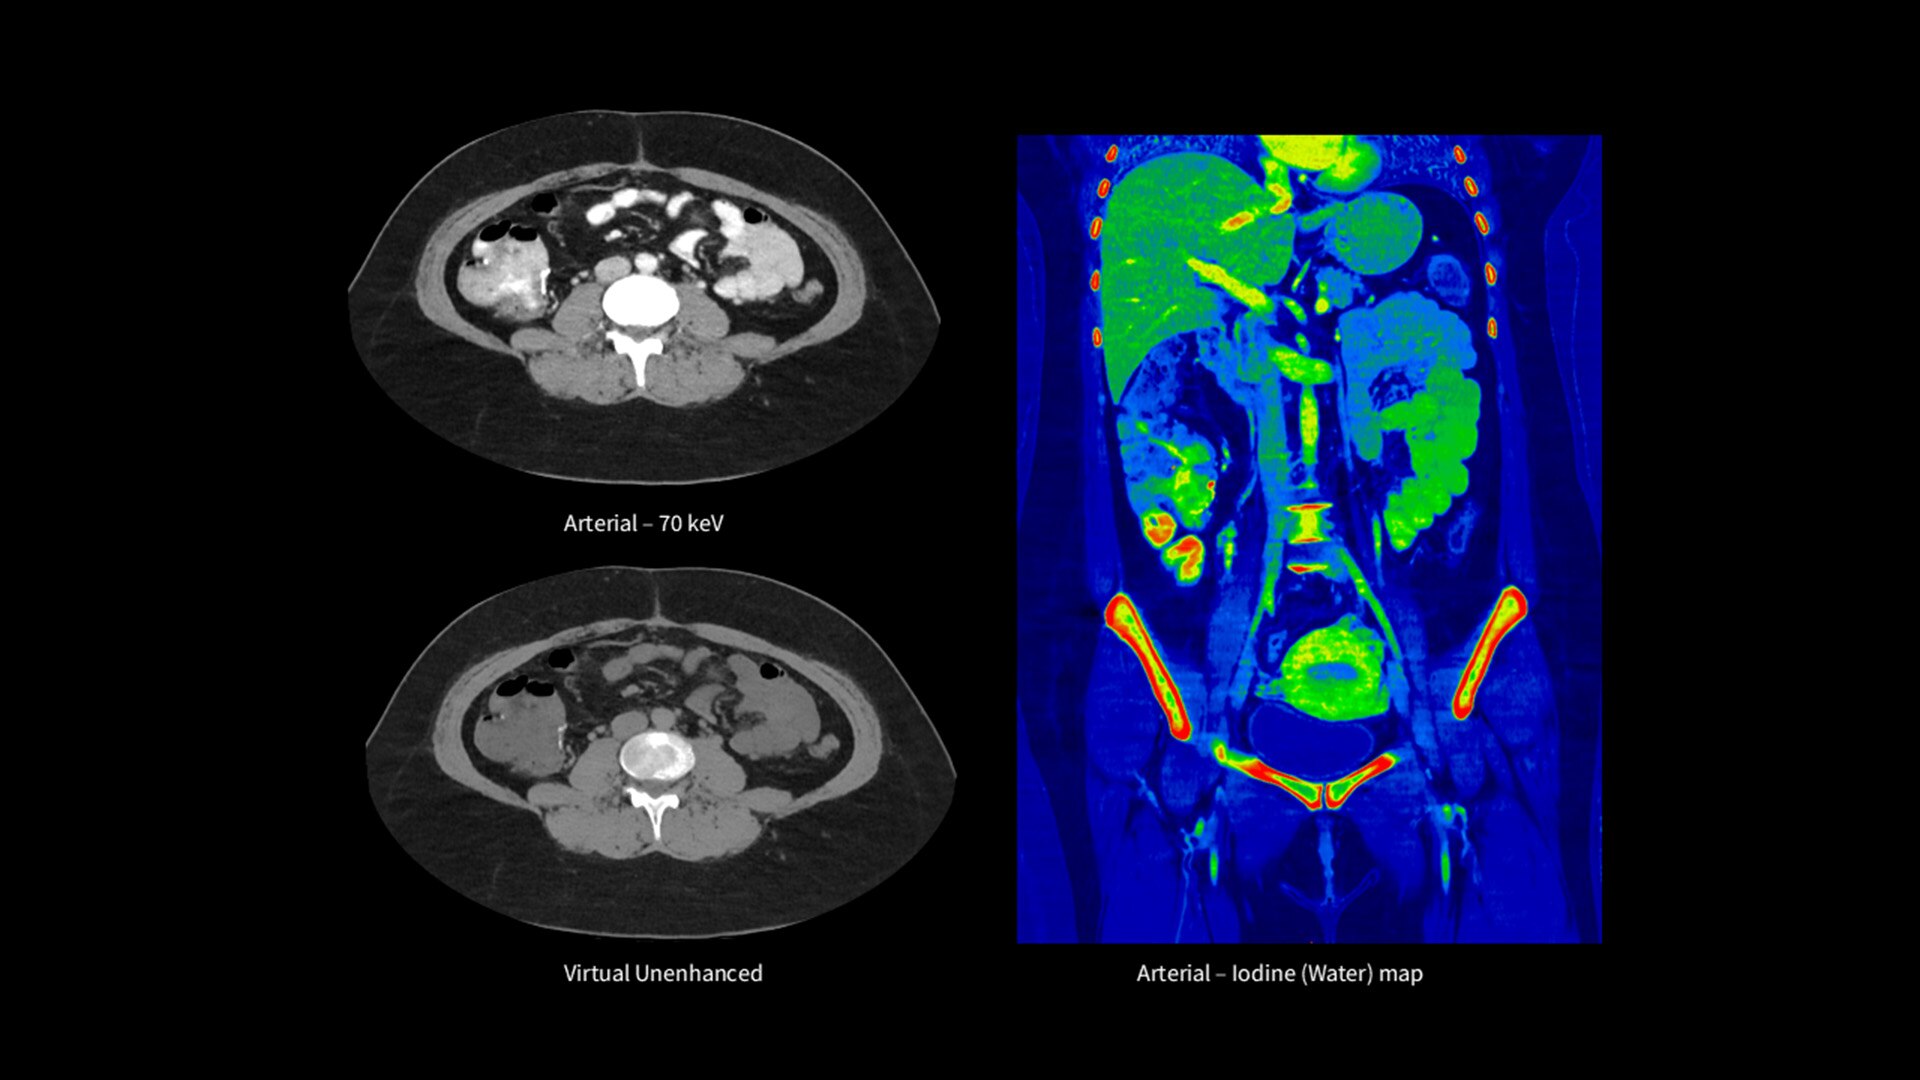

Unlimited 1-Beat Cardiac is designed to provide consistent, high-quality imaging for accurate diagnoses, even in challenging patients with atrial fibrillation, breath-holding difficulties, heavily calcified coronaries, in-stent restenosis, and situations where an ECG trace is unavailable.

Revolution Vibe's AI-powered workflow streamlines the entire cardiac CT process, from pre-scan to post-scan. It delivers accurate, automatically personalized scans for each patient, reducing dependency on user experience and enabling your team to achieve confident results swiftly.